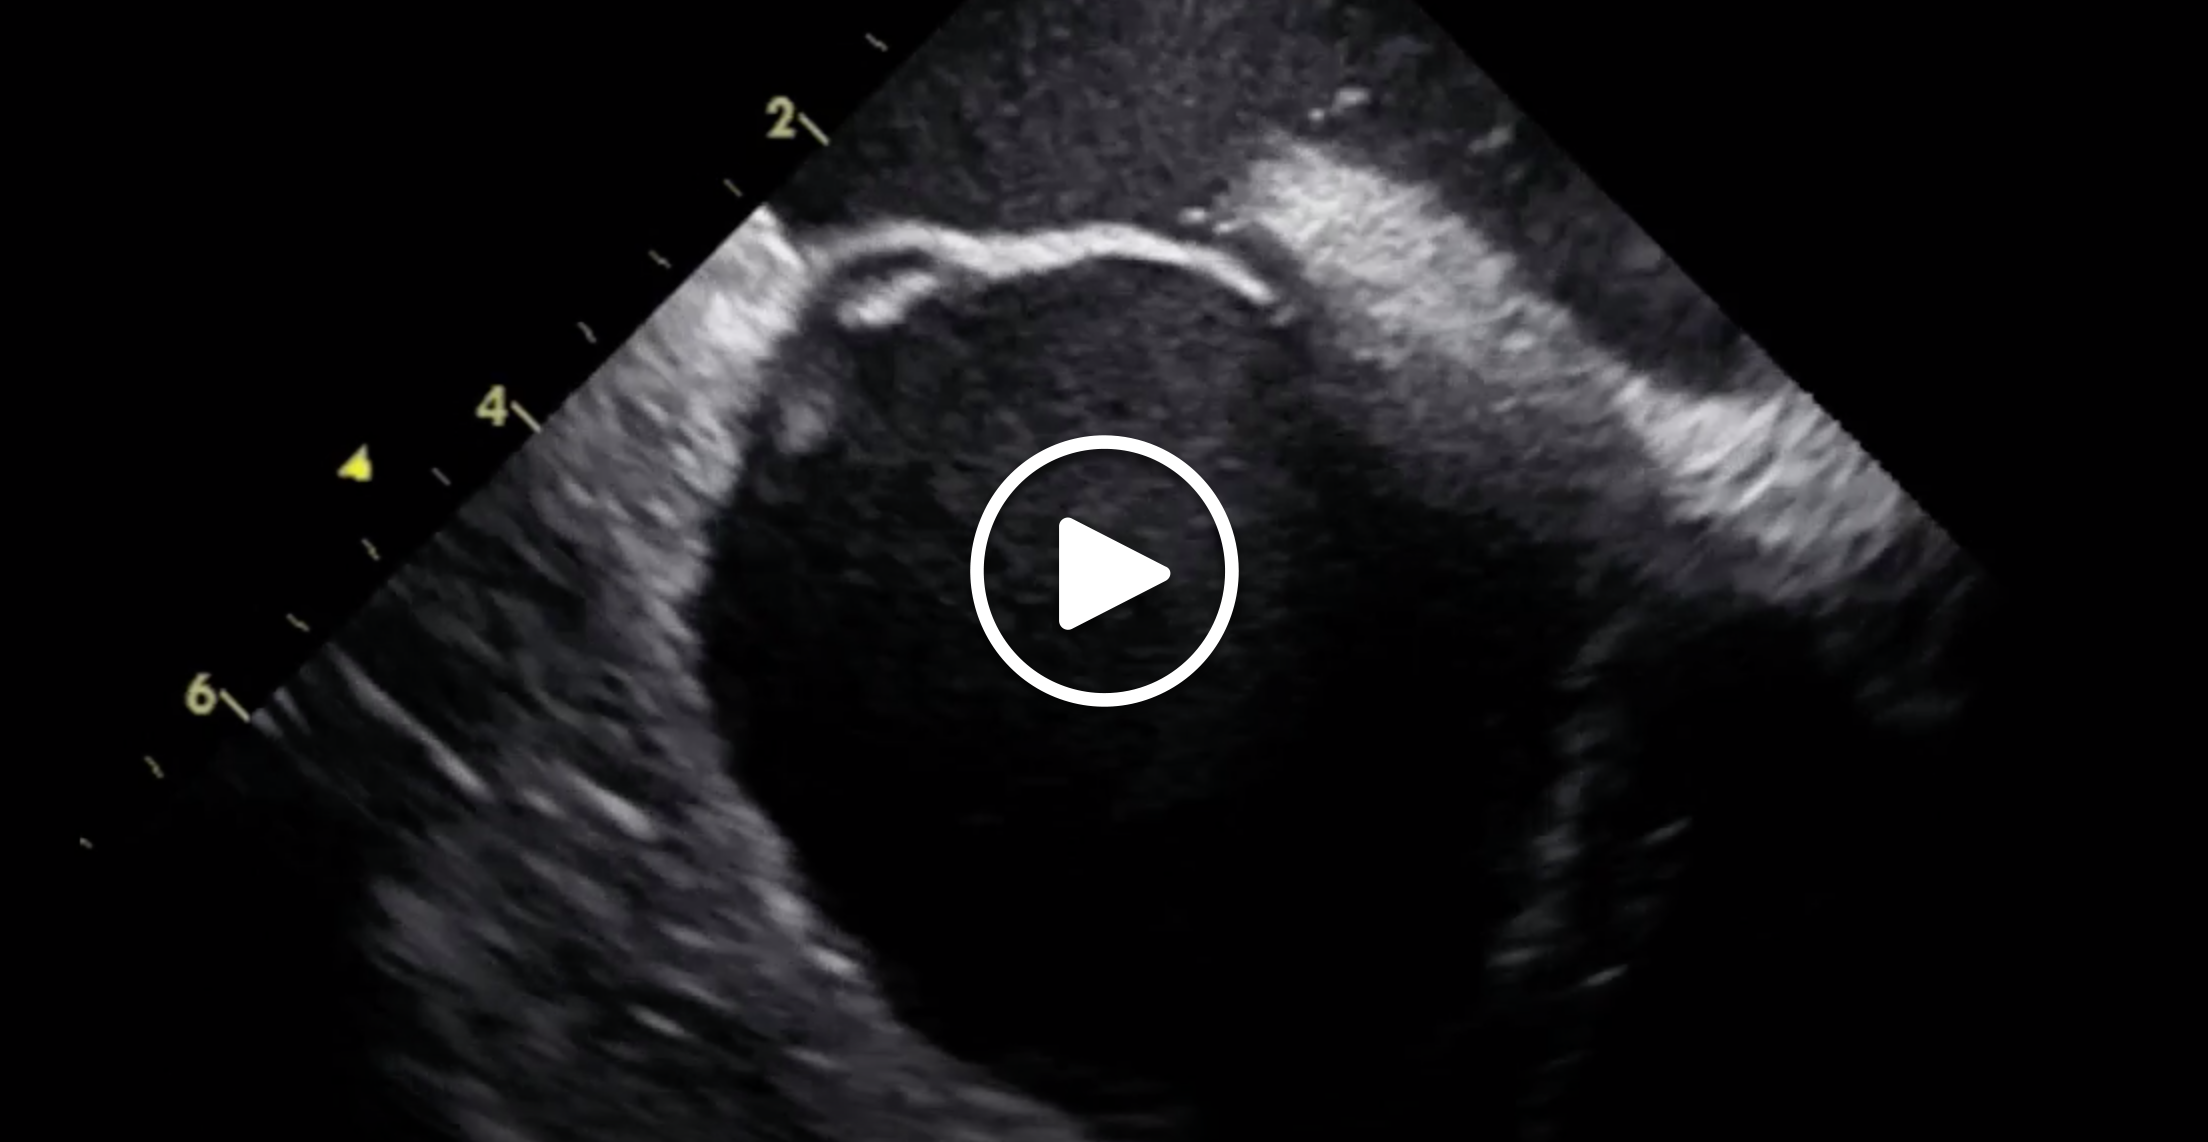

• From the home view, two key views can be obtained to guide PFO closure: (1) the septal (long-axis) view can be obtained by posterior tilting of the ICE probe using the anterior-posterior knob (Figure 1A and 1B); and (2) the aortic (short-axis) view can be obtained by slightly reducing the clockwise rotation of the entire probe and applying a slight right or left tilting using the right-left knob until the tip of the ICE catheter probe is inferior to the aortic valve, just above the tricuspid valve (Figure 1C).

Figure 1. ICE-guided PFO closure with a 25-mm Cardioform septal occluder. Two-dimensional and color Doppler ICE imaging of the PFO in the septal view (long-axis view) (A, B) and the aortic view (short-axis view) (C). Device deployment in the long-axis view (D, E). Final short-axis view after device deployment (F). AV, aortic valve; GSO, Gore Cardioform septal occluder; LA, left atrium; LAx, long axis; Post LA, posterior left atrial wall; RA, right atrium; SAx, short axis; SP, septum primum; SS, septum secundum; SVC, superior vena cava.

We advance the deaired device delivery system over the Amplatz Extra Stiff wire into the left atrium and then remove the Amplatz Extra Stiff wire. The Cardioform septal occluder is typically preloaded into the delivery system, which minimizes the risk of air embolism. However, it is essential to maintain a wet-to-wet connection and avoid deep inspiration when an Amplatzer device is loaded into the delivery system because these situations carry a higher risk of air embolism. Once the device is advanced into the left atrium, the left-sided disc is unsheathed and pulled against the septum (Figure 1D). While maintaining a slight tug on the system, the right-sided disc is unsheathed/deployed, allowing the device to fully bracket the PFO.

The position and seal of the device are confirmed by two-dimensional and color Doppler ICE imaging in the short- and long-axis views. Device-specific securing mechanisms are then applied (tug test for Amplatzer and loop locking for Cardioform), and further evaluation with ICE is performed (Figure 1E and 1F). When satisfactory position, stability, and seal are ensured, the device is released under ICE and fluoroscopic guidance. The procedure is concluded by a final ICE survey with a clockwise sweep of the probe, starting at the home view to rule out pericardial effusion. Hemostasis can be achieved with a figure-of-eight 0 silk suture and additional manual pressure for 5 minutes.